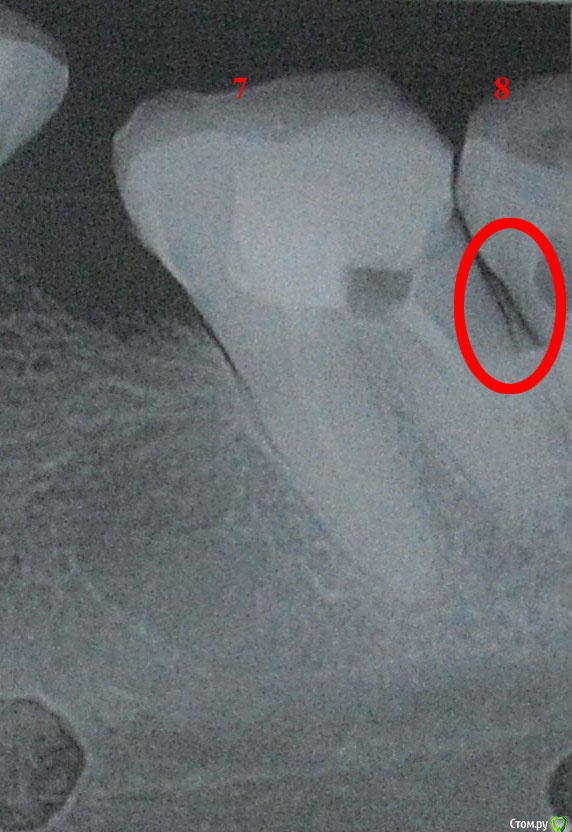

usersha Опубликовано 1 августа, 2019 Поделиться Опубликовано 1 августа, 2019 Здравствуйте! 10 дней назад у меня выступил флюс то есть десна между 7 и 8 зубом слева внизу отекла и появился гнойничек. До этого была боль пульсирующая или как будто распирающая. После того появился флюс боль практически прошла. У врача на приеме сделали снимок. Я думала что причина в 8 зубе так как боль усиливалась при нажатии. Но потом когда боль прошла то и при нажатии боли нет. По снимку врач сказала что корни нормальные и проблема в десне может быть поранила. Хирург сделал надрез сказал чтобы выходила инфекция. Дренаж не ставил. Я полоскала содой солью и пила амоксициллин 8 дней. Отек стал спадать было видно как образуется гнойное типа налета и выходит..... где то дня 4 назад десна стала немного побаливать и я добавила левомеколь - 3 раза в день... и периодически из этого надреза появляется белый налет (гной) потом при полоскании отскакивает. Опухоль в основном спала,но десна слегка увеличена. В основном десна не болит если не теребить ее. Как долго выходит инфекция и проходит флюс? Вторая неделя пошла это долго или это нормальные сроки? И еще вопрос. Пломба у 7 зуба стоит так что с внутренней стороны межзубное пространство забито пломбой и она упирается в десну. Я прочитала что нависающий край пломбы может травмировать десну. Один из способов проверить - зубная нить которая не должна цепляться. Как раз если провести нитью то у самой десны нить как бы цепляется как за крючок что ли. Могла ли эта пломба в межзубном пространстве давящая на десну привести к флюсу? Сейчас там где с внутренней стороны пломба давит в межзубном пространстве я чувствую дискомфорт и немного болезненно у десны. Флюс у меня с внешней стороны ( то есть со стороны щеки) он был расположен как-то прям между зубами 7 и 8 со смещением отечности в сторону 8 зуба. Может ли врач убрать пломбу в межзубном пространстве нависающий край без переделывания всей пломбы? Заранее большое спасибо за помощь! PS первый снимок 7 и 8 зубы, второй снимок 7 зуб и часть 8 Ссылка на комментарий

red_butler Опубликовано 2 августа, 2019 Поделиться Опубликовано 2 августа, 2019 Спасибо за ответ! Скажите а зачем удалять зуб мудрости если он не болит и как сказала врач там корни нормальные? флюс скорее от травмы либо зубной щеткой десны либо от постоянного пломбы в межзубном пространствеВосьмой зуб сильно разрушен, корневые каналы полноценно не пролечены. Контактного пункта с седьмым зубом нет, это привело к воспалению десны и рецидиву кариеса на седьмом зубе. Оставляя зуб мудрости Вы приближаете конец седьмого зуба. 2 Ссылка на комментарий

usersha Опубликовано 6 августа, 2019 Автор Поделиться Опубликовано 6 августа, 2019 Про зубы я Вам ответил. Карман есть.Убистезин нормальный препаратP.s. Надеюсь дизлайк Вы мне поставили ошибочно...нет не ошибочно! вы конечно модератор администратор и можете легко забанить меня! но я все равно скажу! вы не отвечаете по существу! за это и минус! я спросила насчет флюса и его лечения без удаления 8 зуба! все что вы советуете только удалять! причем здоровый зуб! и насчет анастезии я спросила как он совместим в анаприлином! вы отвечаете нормальный препарат! прерасный ответ! в инстукции к убистезину написано противопоказание и несовместимость с неселективными бета-блокаторами а анаприлин как Вам известно это неселективный бета блокатор! поэтому я и спрашивала! и еще меня интересовала это действительно так что лидокаин с адреналином при воспалительном процессе плохо действуют и что при тех же условиях то есть воспалении убистезин действительно лучше действует? я спросила про карман потому что во первых мне никогда пища в межзубном пространстве не застревала! во вторых есть истиные и ложные карманы! в третьих мне ни один из врачей не проверил то есть не зондировал десну чтобы говорить карманы! и наконец по снимку видно что одна и таже часть сильно отличается ! я не спец но видела снимки в сети карманов где идет разрушение кости или как там правильно называется! у меня на одном снимке между зубами четко видна белая полоса а на другом нет! может принтер УДАЛЕНО АДМИНИСТРАТОРОМ в поликлинике как может отличаться одна и таже часть на снимках! вы конечно извините меня за резкость но меня достало что к нам относятся как быдлу! я знаю что на этом форуме мне никто ничего не должен! у нас в этой стране никто уже никому ничего не должен,дальше я помолчу иначе тема сведется к политике. 1 3 Ссылка на комментарий

сирена Опубликовано 9 августа, 2019 Поделиться Опубликовано 9 августа, 2019 Причём убистезин в этом плане выгодно отличается от лидокаина с адреналином,там адреналина меньше.Но вообще у пациентов,принимающих анаприлин лучше использовать скандонест,либо другие безадреналиновые анестетики,но анестезия от них слабее,чем от того же убистезина.Другой выход - проконсультируйтесь у Вашего леч.врача,нельзя ли сменить анаприлин на селективный блокатор,с этими препаратами можно использовать "сильные" анестетики с адреналином.А насчёт кармана,Вам правильно ответили:проблему можно решить только удалением либо седьмого,либо восьмого зуба.Карман из-за длительного отсутствия шестого зуба и смещения седьмого в сторону дефекта зубного ряда.Я думаю - надо с ортопедом посоветоваться,как лучше сделать,имея ввиду будущее протезирование этого сегмента. 1 Ссылка на комментарий